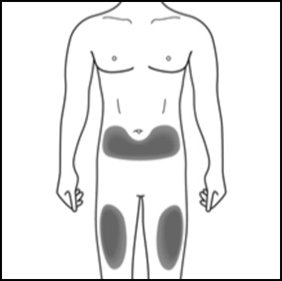

2a. Wählen Sie Ihre Injektionsstelle:

2b. Nur für Betreuungspersonen oder medizinisches Fachpersonal:

Falls eine Betreuungsperson oder eine medizinische Fachperson Ihnen die Injektion verabreicht, kann die Injektion auch an der Außenseite der Oberarme erfolgen.